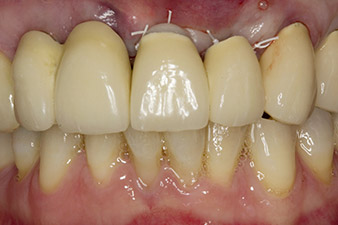

Imagen. 1: Los resultados radiológicos iniciales mostraban una pieza con una corona bloqueada que debía reemplazarse. Durante la extracción, se extrajeron por accidente las piezas dentales 21 y 22.

En la primera visita se trataron las piezas 21, 22 y 23, que presentaban bloqueo en las coronas colocadas hacía 19 años. Estas estaban unidas mediante una férula con los implantes de las posiciones 12/11 (figura 2). La imagen radiológica muestra una pérdida ósea horizontal alrededor de las piezas dentales 21 y 22 (figura 1).